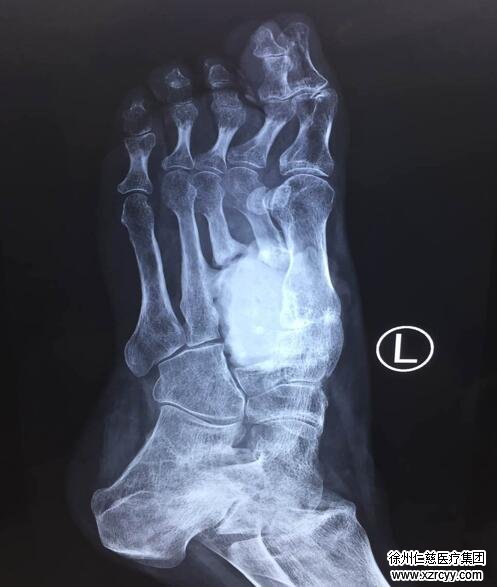

经过一段时间的康复和休整,今年2月,常女士再次入院,取除左脚骨折的内固定装置。然而让医护人员和患者不愿看到的是,术后常女士脚上的伤口迟迟未能愈合,经医生确诊,这是由于常女士患上了骨髓炎并迁延不愈所导致,必须对骨髓炎病灶进行彻底清除,才能进行骨移植,保证患足真正意义上的治愈。于是又经过半年的清创和恢复,常女士于近日接受了跖骨游离腓骨的移植修复手术。在医护人员的全程护航下,目前移植的骨头已经基本长好,患足血液供应情况良好,待伤口基本愈合后即可出院。